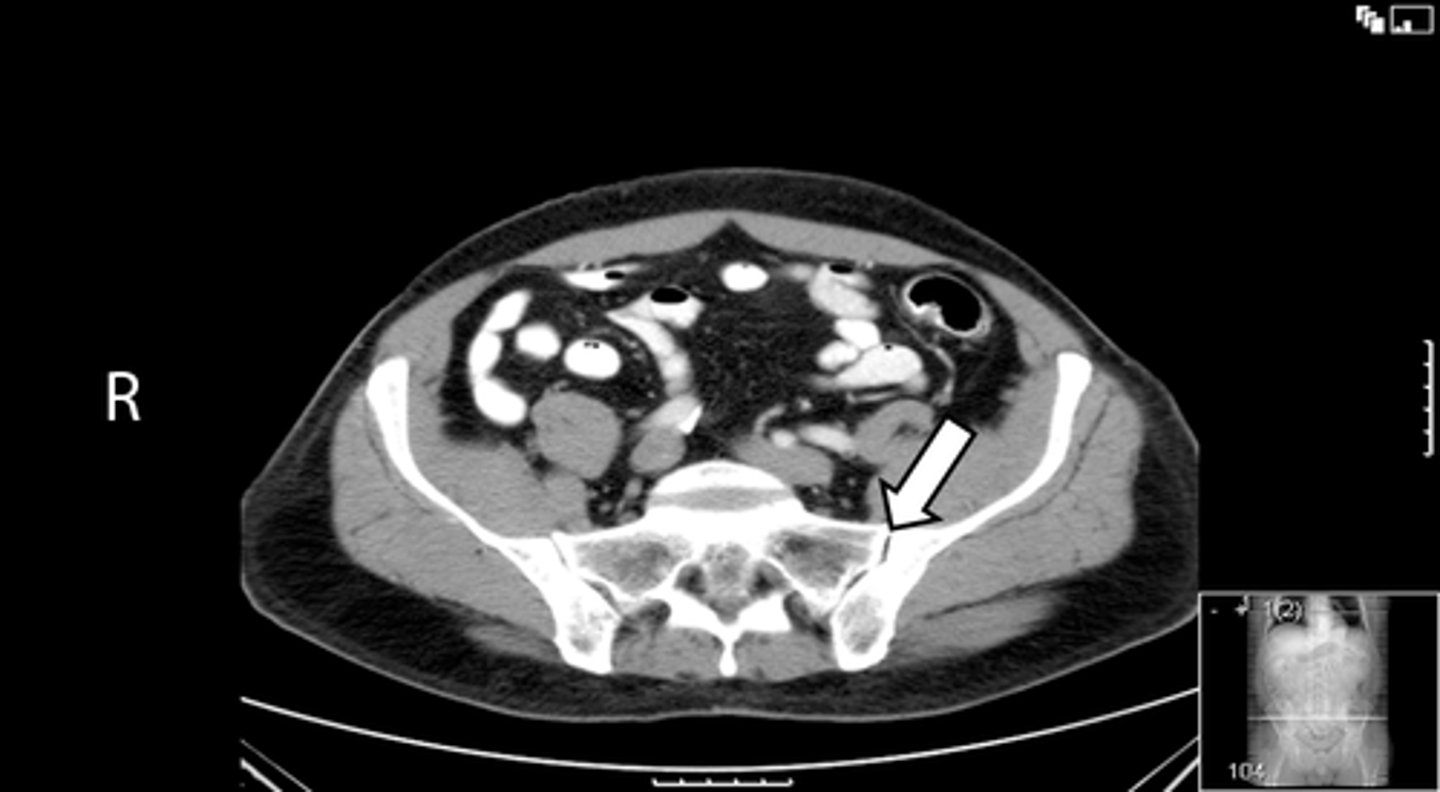

Axial bony pelvis CT

What is the image?

32

L ilium

What is indicated in the image?

<p>What is indicated in the image?</p>

New cards

L sacroiliac joint

34

R ilium

R sacroiliac joint

36

Sacrum